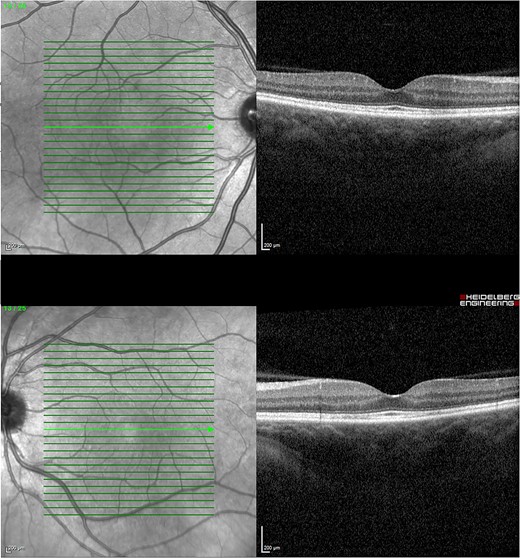

Given the clinical features, the patient was diagnosed with VKH-like syndrome, presumably secondary to MEK and BRAF inhibitor therapy. In consultation with her oncologist, dabrafenib and trametinib were withheld. She was admitted and promptly started on pulsed methylprednisolone 1 g daily for 3 days. Autoimmune and infective screens were all negative. Magnetic resonance imaging of the brain with contrast had no evidence of cerebral vasculitis. The patient responded well to methylprednisolone with BCVA of 6/9–1 in the right eye and 6/30 in the left after 3 days. Subsequently, she was started on a slow tapering dose of oral prednisolone of 5 mg weekly with a starting dose of 65 mg daily. In conjunction with the oncologist, dabrafenib was reintroduced at 150 mg twice daily after being withheld for 2 weeks. Trametinib was reintroduced at a lower dose of 0.5 mg daily and was slowly up titrated to 1 mg after being withheld for 4 weeks. Her BCVA and OCT were monitored monthly, illustrating a progressive decline in ONHS and subretinal macular fluid. Four months later, her BCVA recovered to 6/6 in both eyes with no evidence of active uveitis and completely resolved subretinal fluid while on a maintenance dose of 10 mg prednisolone daily (Fig. 4).

OCT 4 months post treatment showed complete resolution of fluid and reinstitution of normal retinal architecture.